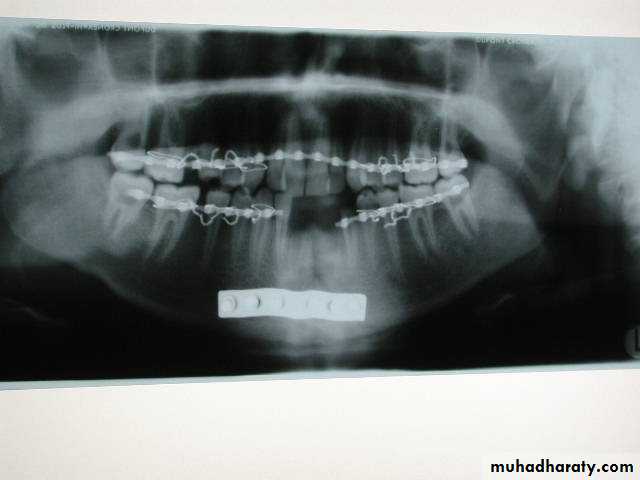

• Closed reduction : Dependent on splinting of the mandible to maxilla to restore centric occlusion (maximal inter cuspation)• 1. IMF ( Prefabricated arch bar )

Arch bars

Jelenko

Erich pattern

German silver notched

▶ IMF prior to rigid fixation

▶ For the purpose of close reductionClose reduction

• Rigid internal fixation (plating) these method use bone plates, bone screws or both to fix the fracture.

Rigid fixation

Intraossous wiringPlates and screws

Plating

If teeth are present IMF is done ; then incision is made and bone is reached either extra orally or intra orally.

The fractured ends are approximated and screw holes are made such that at least 2 screws can be placed on either side of the fracture.